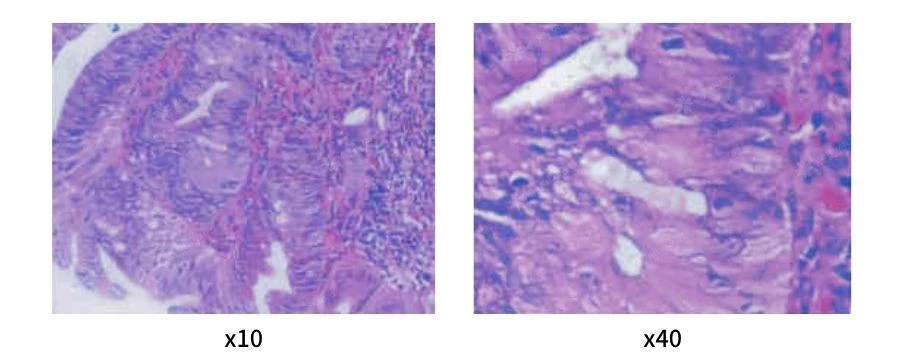

Kết quả sinh thiết cho thấy tân sản tuyến với đặc điểm nhân tăng sắc kiềm, hạt nhân lớn, có hình ảnh nhân chia không điển hình. Tế bào sắp xếp thành cấu trúc tuyến ống và nhánh, có hiện tượng xâm nhập tế bào viêm.

Chẩn đoán mô bệnh học xác định tổn thương là u tuyến ống nhánh, nghịch sản độ cao, có nguy cơ tiến triển thành ung thư nếu không được xử trí kịp thời.